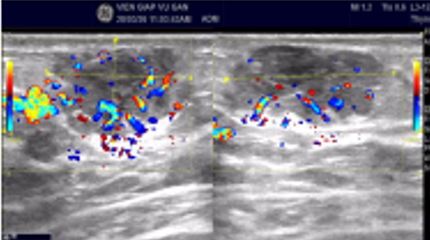

Kết quả siêu âm

Đặc điểm tổn thương

- Kích thước: 27x23x14mm

- Echo kém, không đồng nhất

- Bờ đa cung lớn

- Tăng sinh mạch máu quanh bướu

- Không vi vôi hóa

👉 Phân loại: BIRADS 4C (nghi ngờ ác tính cao)